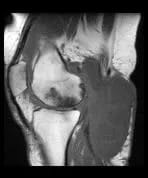

Popliteal Cyst

A patient presents with pain at the back of the knee.

There is a large posterior popliteal fluid collection. Marked tri-compartmental degenerative change in the medial joint compartment is also seen. These latter changes are in keeping with secondary avascular necrosis. Also present is a large joint effusion with marked synovitis and synovial hypertrophy.